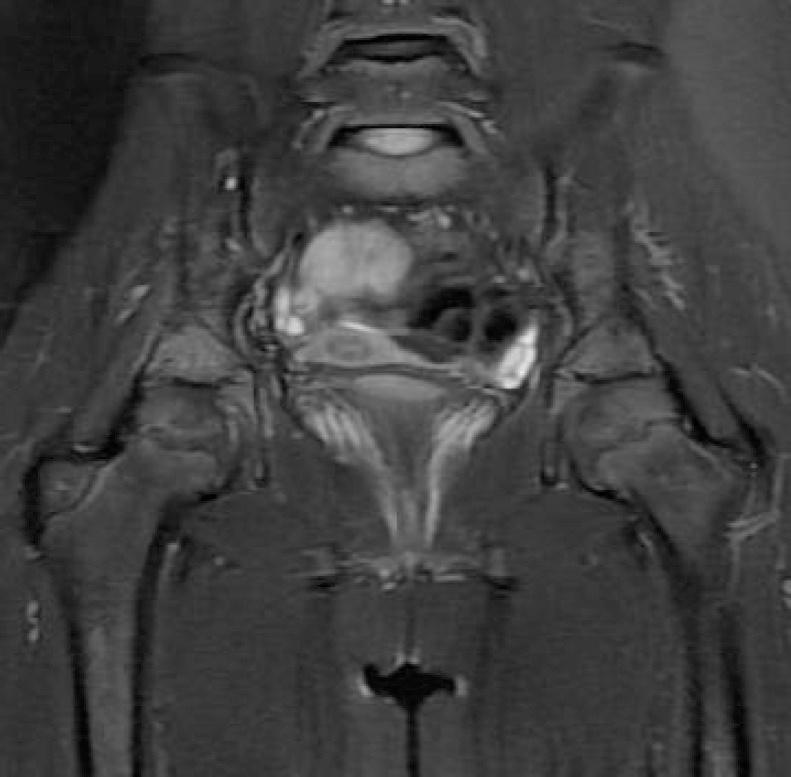

Synovitis, Acne, Pustulosis, Hyperostosis, and Osteitis (SAPHO) Syndrome in Childhood; A Rare Clinical Entity.

Iran J Pediatr. 2014 Oct;24(5):658-9. Epub 2014 Aug 15.

PMID:25793079

原文链接:https://pmc.ncbi.nlm.nih.gov/articles/PMC4359425/